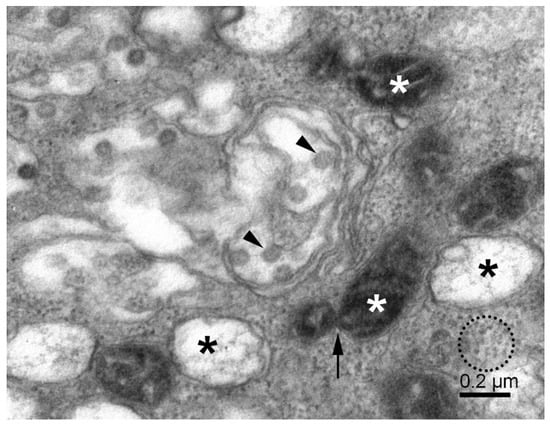

3.2. Mitochondria, Fission, and Mitophagy

3.3. Phagophore, Phagosomes, and Autophagy